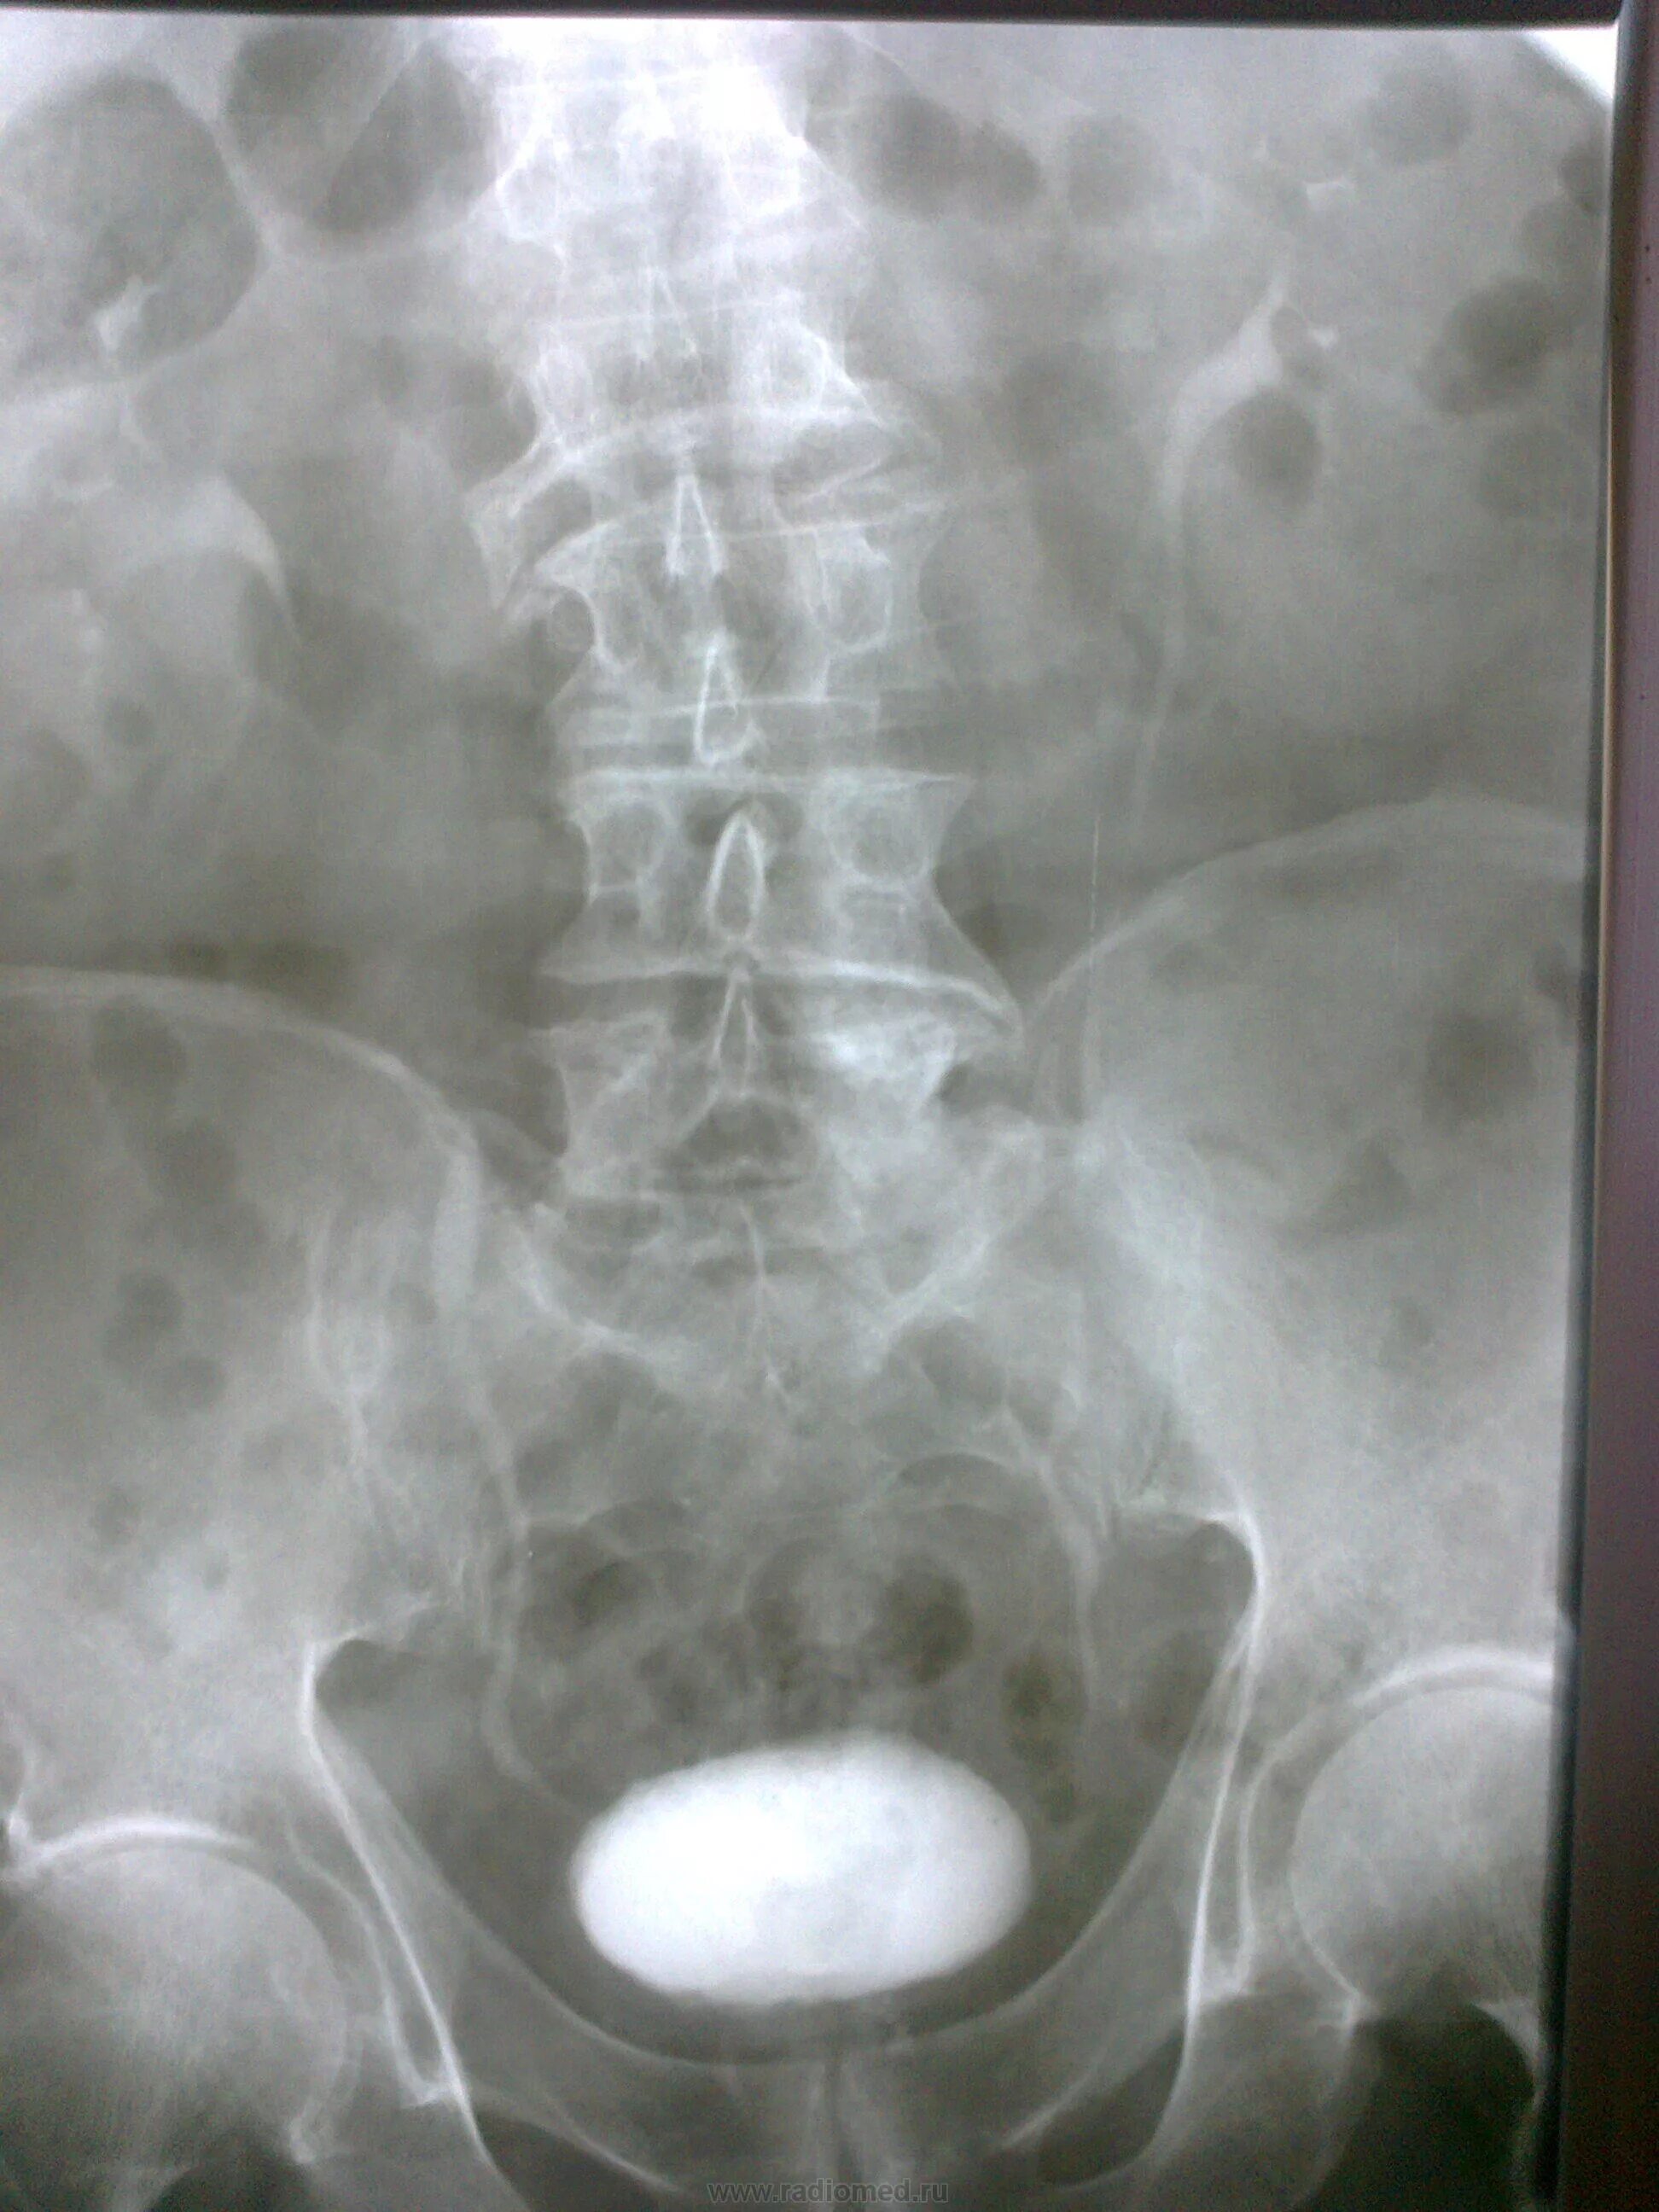

После урографии